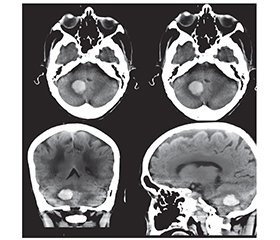

Актуальність. Інсульт є гетерогенним синдромом, і визначення факторів ризику та лікування залежить від його патогенезу. Відомо, що захворювання серцево-судинної системи є факторами ризику розвитку гострих порушень мозкового кровообігу. Згідно з останніми дослідженнями, третина всіх ішемічних інсультів є кардіоемболічними. Фібриляція передсердь та гіпертензія часто співіснують, підвищуючи ризик тромбоемболічних ускладнень і серцевої недостатності. Основною ж патоетіологією геморагічного інсульту у вигляді внутрішньомозкових крововиливів є хронічна гіпертензія та церебральна амілоїдна ангіопатія. Виникнення геморагічного інсульту на фоні фібриляції передсердь у поєднанні з артеріальною гіпертензією є досить рідкісним явищем і створює проблему у виборі стратегії лікування. Метою дослідження було визначення оптимальної тактики лікування складного випадку геморагічного інсульту на тлі фібриляції передсердь у поєднанні з гіпертонічною хворобою. Матеріали та методи. Ми представляємо клінічний випадок геморагічного інсульту, що розвинувся у 84-річної жінки на тлі фібриляції передсердь у поєднанні з гіпертонічною хворобою. Основним питанням, яке постало перед кардіоневрологічною командою, було призначення пероральних антикоагулянтів. З одного боку, пацієнтка мала показання до їхнього призначення згідно з чинними клінічними настановами (оцінка за шкалою CHA2DS2-VASc 6 балів), з іншого боку, наявність геморагічного інсульту є протипоказанням. Результати. Цей випадок демонструє вирішення складного питання щодо вибору тактики лікування геморагічного інсульту й профілактики вторинних ускладнень фібриляції передсердь у поєднанні з артеріальною гіпертензією. Після проведення медикаментозної кардіоверсії з огляду на клінічні рекомендації щодо лікування геморагічного інсульту, а також позитивну динаміку неврологічного статусу пацієнтці було призначено апіксабан у дозі 2,5 мг 2 рази на добу під контролем коагулограми з 7-го дня від початку захворювання. Висновки. Ми вважаємо, що необхідно ретельно проводити неврологічний огляд та оцінку когнітивних функцій в усіх пацієнтів із фібриляцією передсердь, а також розглядати виконання нейровізуалізації до призначення антикоагулянтної терапії. Ми рекомендуємо розглянути призначення пероральних антикоагулянтів пацієнтам після внутрішньомозкового крововиливу, які мають низький ризик його рецидиву й високий ризик розвитку тромбоемболічних ускладнень.

Background. Stroke is a heterogeneous syndrome, and identification of risk factors and treatment depends on the specific pathogenesis of the disease. Cardiovascular diseases are risk factors for the development of acute disorders of cerebral circulation. According to recent studies, one third of all ischemic strokes are cardioembolic. The main pathoetiology of a hemorrhagic stroke in the form of intracerebral hemorrhages is chronic hypertension and cerebral amyloid angiopathy. The occurrence of a hemorrhagic stroke against the background of atrial fibrillation in combination with hypertension is a rather rare phenomenon and poses a problem in the choice of treatment for such patients. The aim was to determine the optimal treatment for a complex case of a hemorrhagic stroke with atrial fibrillation in combination with hypertension. Materials and methods. We present the clinical case of an 84-year-old woman who developed a hemorrhagic stroke on the background of atrial fibrillation in combination with hypertension. The main issue the cardio-neurological team faced was the administration of oral anticoagulants. On the one hand, the patient had indications for their administration according to current clinical guidelines (CHA2DS2-VASc score of 6 points); on the other hand, the presence of a hemorrhagic stroke is a contraindication. Results. This case demonstrates the solution to the difficult issue of choosing treatment for a hemorrhagic stroke and prevention of secondary complications of atrial fibrillation in combination with hypertension. After medical cardioversion, using clinical recommendations for the treatment of a hemorrhagic stroke, as well as given the positive dynamics of the neurological status, the patient was prescribed apixaban at a dose of 2.5 mg twice a day under the control of a coagulogram from the 7th day of the disease onset. Conclusions. We believe it is necessary to perform a thorough neurological examination and assessment of cognitive functions in all patients with atrial fibrillation, as well as to consider neuroimaging prior to the prescription of anticoagulant therapy. We recommend considering the administration of oral anticoagulants to patients with a low risk of recurrence and a high risk of thromboembolic complications after intracerebral hemorrhage.